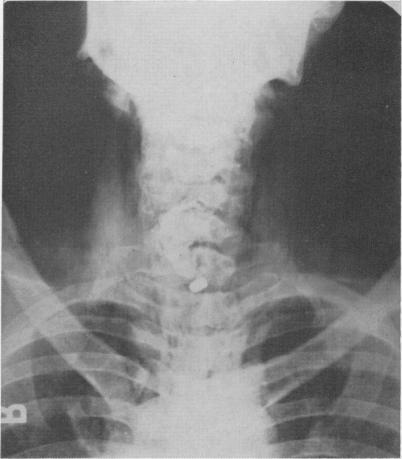

FOSTER J H, JOLLY P C, SAWYERS J L, DANIEL R A

Ann Surg. 1965 May;161(5):701-9. doi: 10.1097/00000658-196505000-00008.